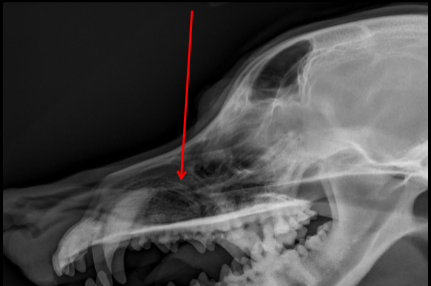

Frontal Sinus

ID

Zygomatic Arch

Maxillary Bone

Temporomandibular Joint